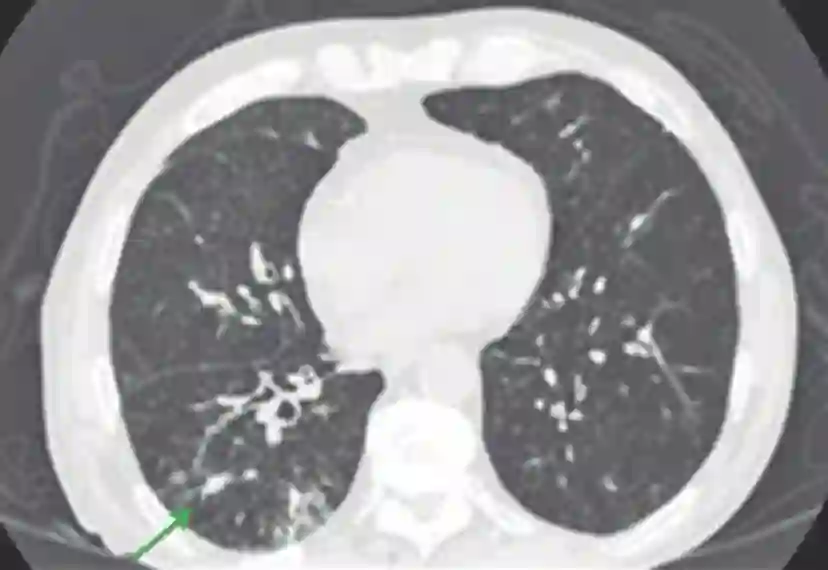

患者是一名73岁的老年男性,左大腿存在黑色素瘤病灶。病人在发病早期就接受了局部切除治疗,并在日后的过程中坚持随访。直到术后第8年,病人检查出了肺部的黑色素瘤转移病灶,其开始使用达卡巴嗪和伊匹木单抗进行治疗,但是病情的进展过程并没有被抑制,因此,病人开始使用帕博利珠单抗每3周2mg/kg的方案进行治疗。但是在第一次治疗后的14天时,病人开始出现干咳(无其他症状),CT检查显示其双侧肺部都出现了磨玻璃样改变。病人被确诊为帕博利珠单抗导致的肺炎,并迅速接受了1mg/kg强的松联合抗生素的治疗,万幸的是病人的肺部症状在用药治疗后出现 了明显的好转。2个月后,病人的肺部炎症反应被完全治愈,并对持续进行的帕博利珠单抗治疗表现出了良好的耐受性。